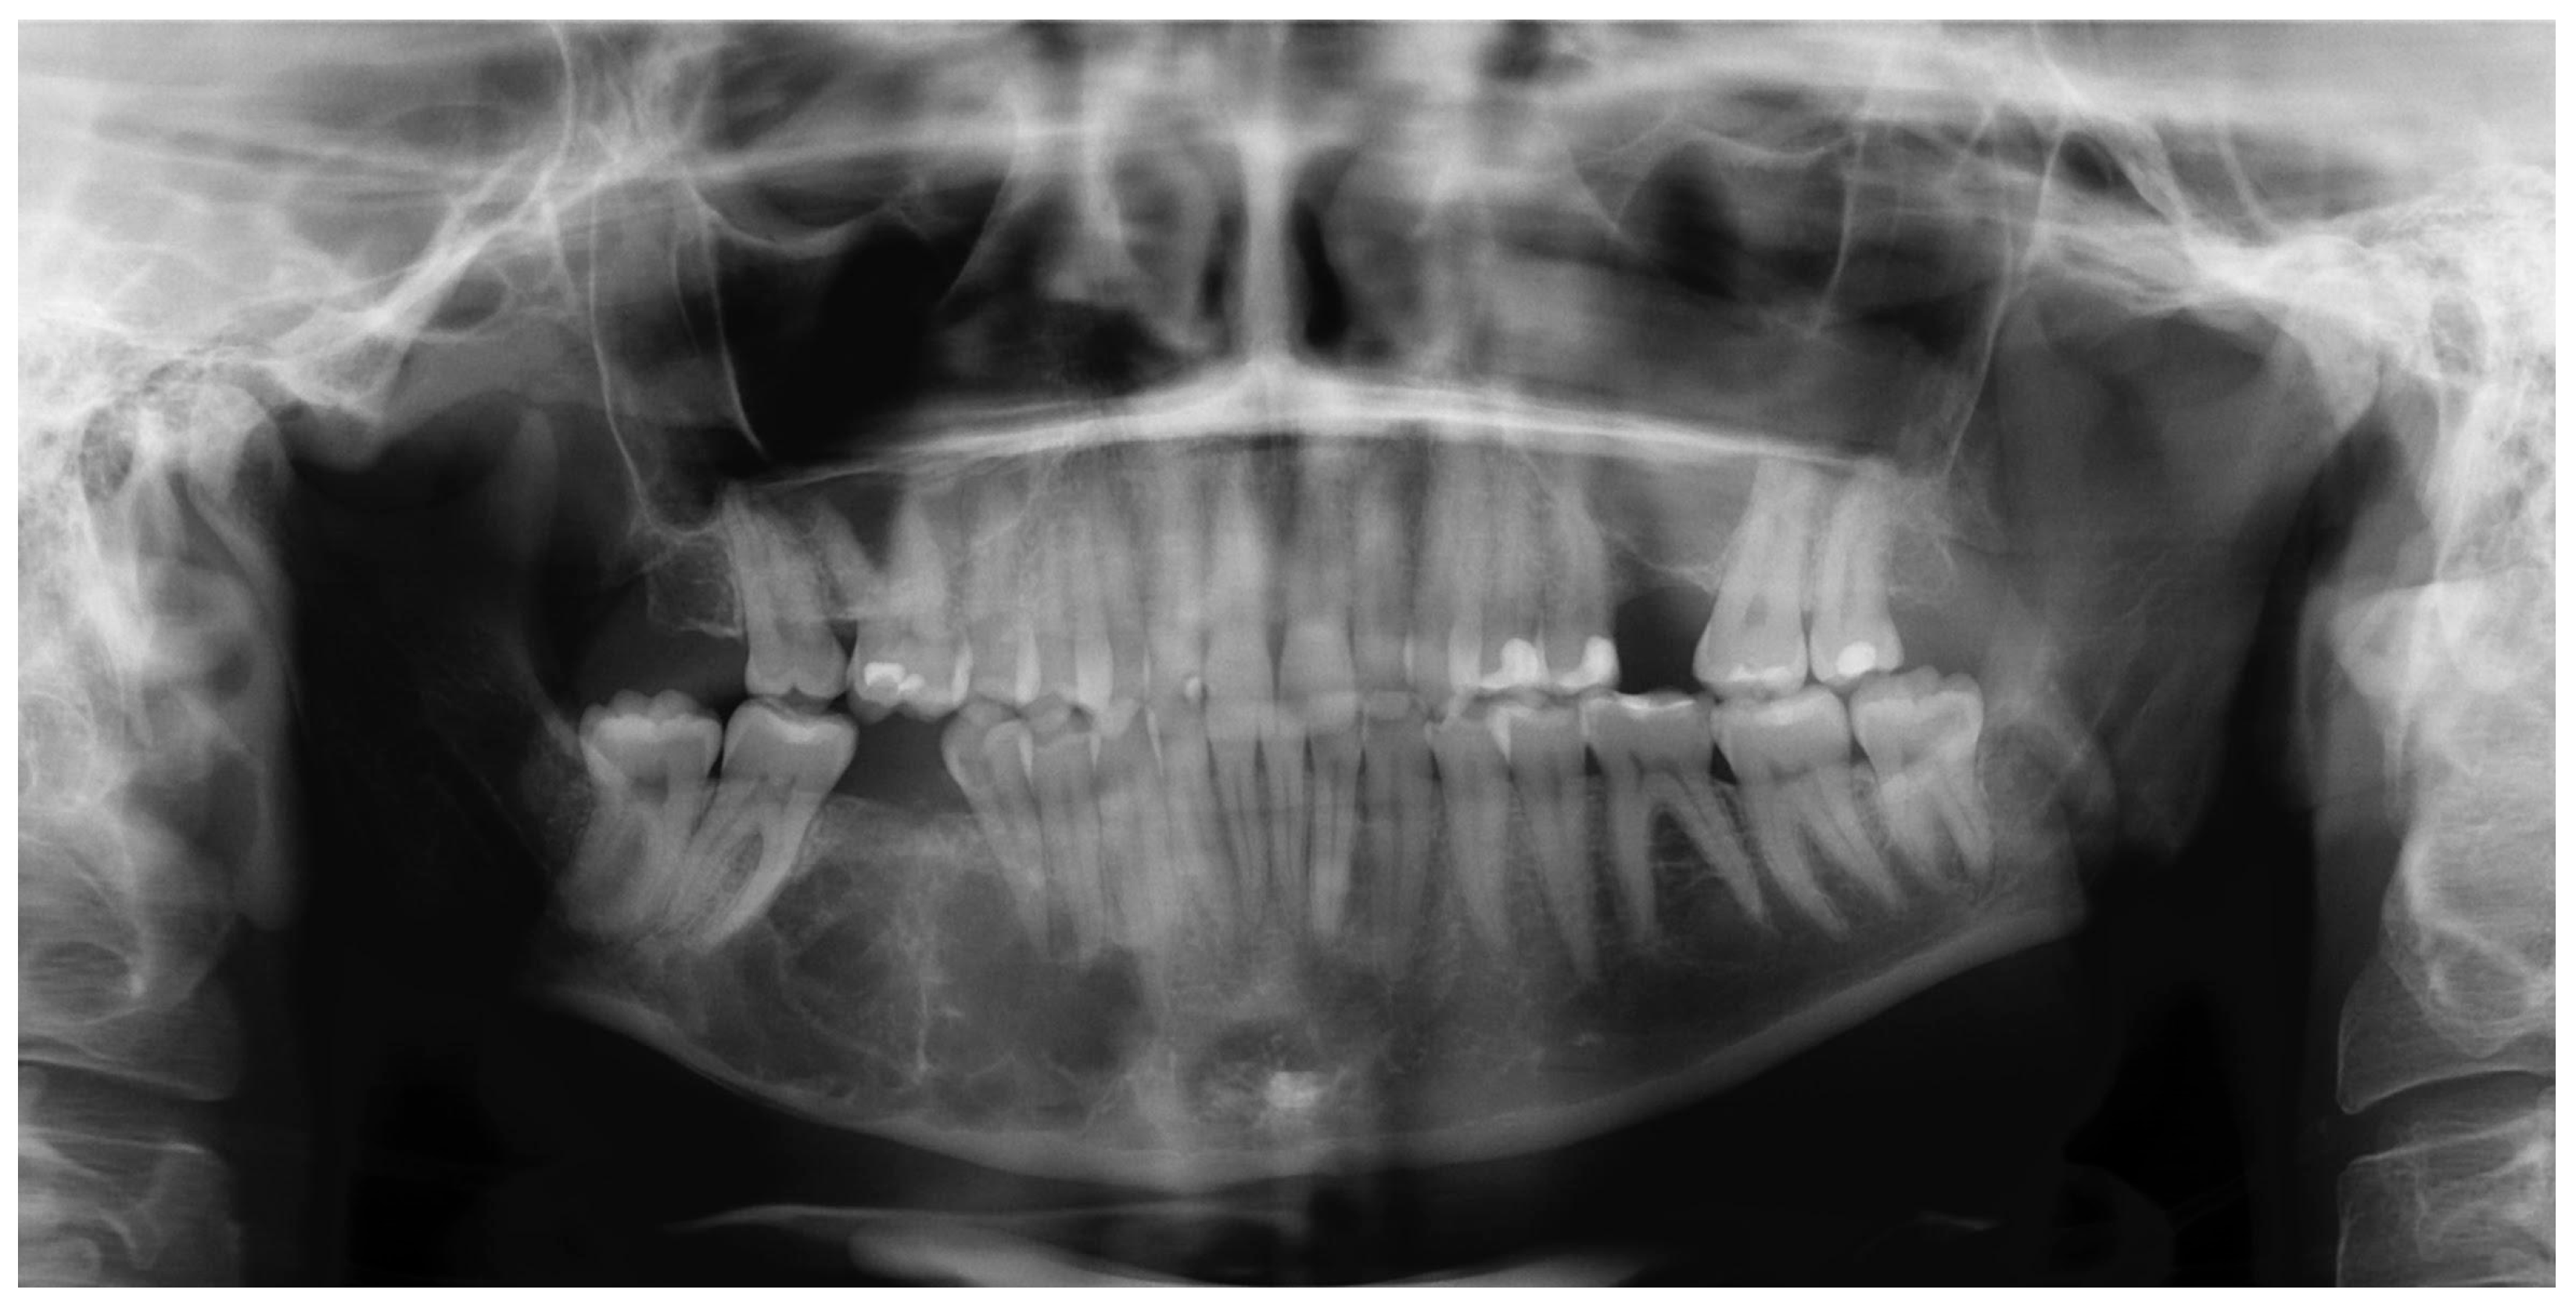

2. Case Report

2.1. Examination

2.2. Treatment Procedures and Histopathological Results